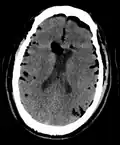

Pneumocephalus and comminuted fracture of the frontal sinus

Pneumocephalus is the presence of air or gas within the cranial cavity. It is usually associated with disruption of the skull: after head and facial trauma, tumors of the skull base, after neurosurgery or otorhinolaryngology, and rarely, spontaneously. Pneumocephalus can occur in scuba diving, but is very rare in this context.

CT scans of patients with a tension pneumocephalus typically show air that compresses the frontal lobes of the brain, which results in a tented appearance of the brain in the skull known as the Mount Fuji sign.[1][2][3] The name is derived from the resemblance of the brain to Mount Fuji in Japan, a volcano known for its symmetrical cone. In typical cases, there is a symmetrical depression near the midline (such as the crater of a volcano), due to intact bridging veins.[3] Its occurrence seems to be limited to tension pneumocephalus (not occurring in pneumocephalus without tension).[4] The sign was first described by a team of Japanese neurosurgeons.[5]